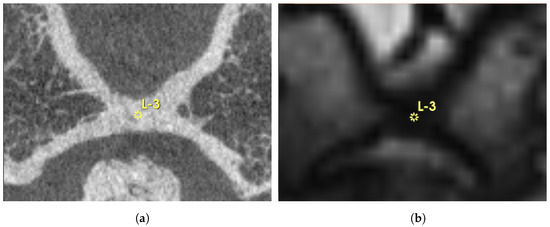

As shown in Figure 1, manual landmark-based alignment was performed using pre-defined points on both fixed and moving images based on anatomical structure landmarks of semicircular canals. A Versor Rigid 3D transform was initialized based on these landmarks to refine the initial transformation. This transformed the Euler 3D transformation to optimize the alignment based on landmarks.

Figure 1.

Exemplary overview of a landmark defined in 3DSlicer (yellow “L-3”) in axial (a) and sagittal view (b). As the Euclidean distance of the landmarks increases, the transformation becomes more accurate. Bilaterally, the tip of the anterior semicircular canals was also chosen. The high-resolution DynaCT is depicted in (a,c), whereas the T2-weighted MRI is shown in (b,d).